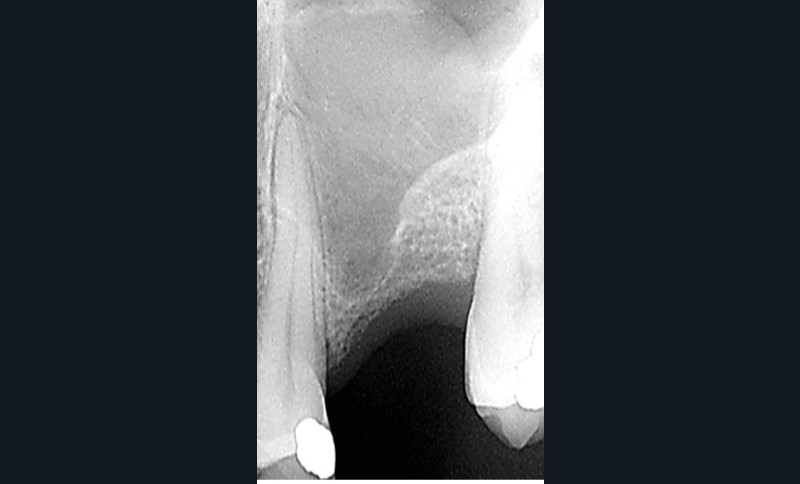

L’étude conduite à Bordeaux vise à valider une nouvelle forme d’ostéotome (fig. 2) dont l’architecture permettrait un protocole plus efficient en termes d’impaction et de fracture du fragment osseux sous-sinusien sans déchirure de la membrane. Trente-trois pièces anatomiques humaines fraîches [2] ont été utilisées pour réaliser des élévations sinusiennes par voie crestale de 4 et 8 mm en utilisant le protocole décrit avec cet instrument. L’intégrité et le comportement de la membrane sinusienne ont été analysés et les résultats montrent l’efficacité du protocole…